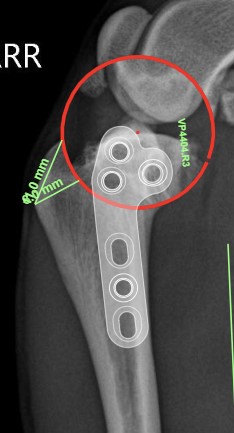

해당 케이스에서는 호흡 마취하에 TPLO(Tibial Plateau Leveling Osteotomy) 수술을 진행했습니다.

미래동물의료센터에서는 TPLO 수술 전 시뮬레이션 프로그램을 활용해

사용할 플레이트와 스크류의 크기, 경골의 회전 각도와 이동 거리를 미리 계산한 뒤 수술을 계획합니다.

이 과정은 수술 정확도를 높이고 술 후 회복을 안정적으로 만드는 데 중요한 단계입니다.

수술 전 시뮬레이션 사진 / 출처: 미래동물의료센터

수술 후 방사선 사진 / 출처: 미래동물의료센터

수술은 사전 시뮬레이션 계획에 따라 안정적으로 진행되었으며, 수술 직후에는 통증과 염증 반응을 최소화하기 위해 진통 및 항염 처치를 집중적으로 시행하였습니다. 절개 부위 보호를 위한 드레싱 처치와 함께 수술 초기에는 경골과 임플란트에 과도한 부하가 가해지지 않도록 절대 안정 및 활동 제한을 병행하였습니다.